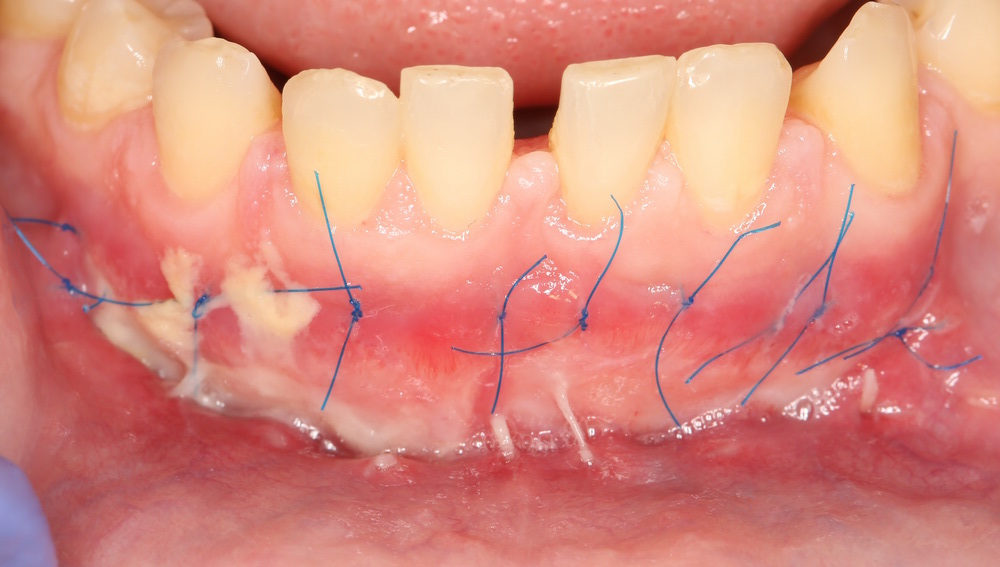

Назначаем осмотр через день. Вот нормальная картинка после подобной операции:

После операции Мукографт пропитался кровью, которая свернулась и осталась в нем, образовав сверху пока тонкую фибриновую пленку. Это еще не слизистая оболочка, а та же матрица, удерживающая «в себе» кровяной сгусток. То есть, своего рода, такой же спейсер, как и Bioss.

При этом, несмотря на масштаб операционной раны, пациентку почти (кроме небольших синяков) ничто не беспокоит. Боли и отека нет.

Фотография через 4 дня после операции:

Фибриновый налет становится толще, из-за чего рана принимает характерный вид. Многие пациенты путают его с гноем, пугаются и пытаются счистить. Конечно же, делать этого нельзя. Фибриновая пленка это, своего рода, защитная повязка, которая предохраняет регенерирующие ткани от внешних воздействий.